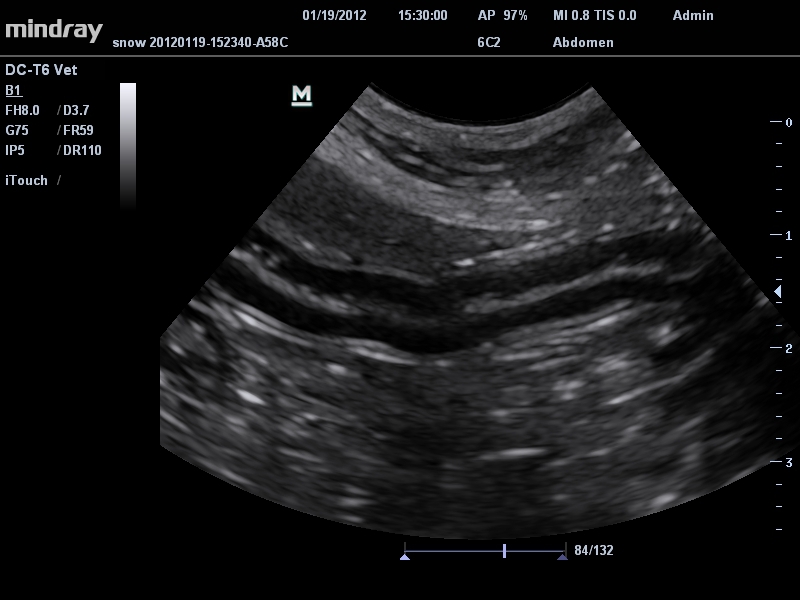

Mindray DC-T6

Ультразвуковая система Mindray DC-T6 – это инновационный аппарат для проведения высокого уровня диагностики с качественной визуализацией и широким спектром применения. Платформа рекомендована для использования в коммерчески многопрофильных медицинских учреждениях и государственных лечебных клиниках.

Ветеринария:

Да